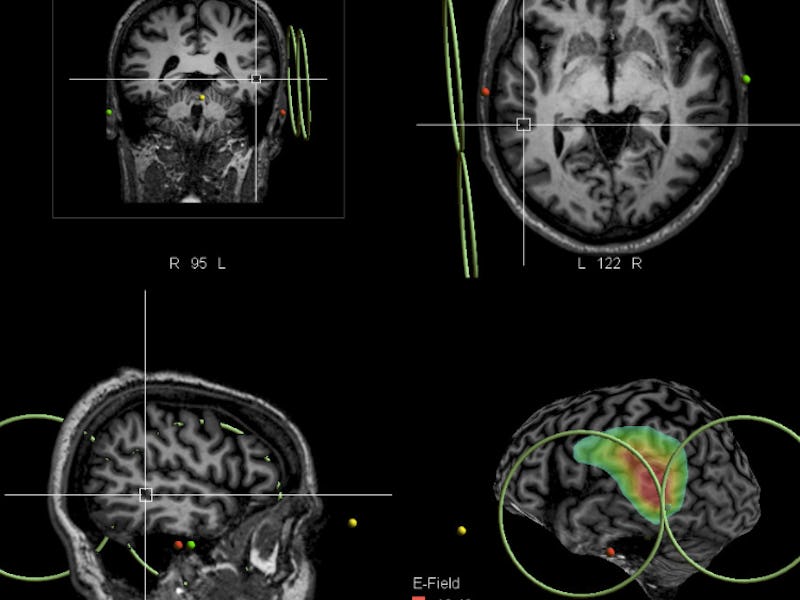

A French research group targeted the brain’s left temporal cortex, an area that they precisely identified as being involved in the experience of hearing voices. The exact area — the projection of the ascending branch of the left lateral sulcus that crosses the left superior temporal sulcus — is a part of the brain that’s associated with language. Using Transcranial Magnetic Stimulation (TMS) — a process that involves zapping specific areas of the brain with electromagnetic pulses — researchers gave 26 patients a series of 20 Hz high-frequency pulses over 2 sessions a day for 2 days. They also administered a sham treatment to 33 other patients with schizophrenia, and then compared the outcomes.

A magnetic stimulation is applied via the blue device onto a localized brain area in real time,.